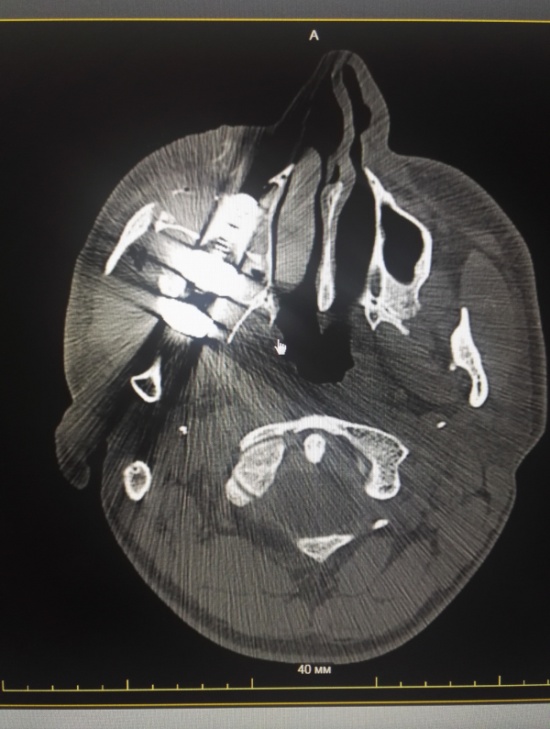

Мужчина получил мощный удар по голове и упал на землю. К счастью, остановился проезжающий мимо водитель легкового автомобиля, усадил пострадавшего в свою машину и довез до Лесосибирской городской больницы. Врачи обработали рану, а сделав снимки, увидели 6-сантиметровый болт, который находился внутри верхне-челюстной пазухи.

Врачи провели операцию и извлекли болт из головы. Медикам удалось спасти глаз пациента, но ему все же придется пройти курс лечения в краевом офтальмологическом центре, чтобы полностью восстановить зрение.